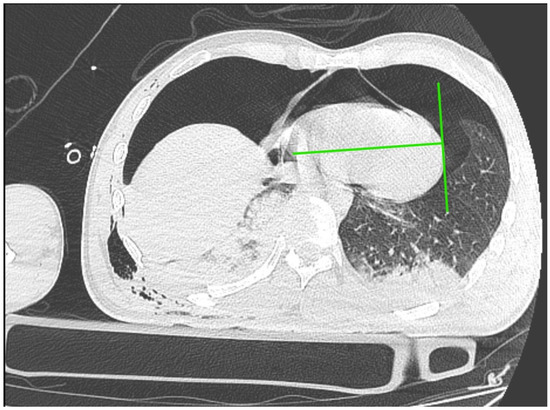

Immediately after decompression, the blood pressure was 134/85 mmHg, the heart rate was 105 bpm, and the saturation was 92%. The critical parameters from the blood gas analyzer just after the decompression of pneumothorax are as follows (11:15 p.m.): pH 7.016, pCO2 45.2 mmHg, pO2 107 mmHg, HCO3 11.6 mmol/L, BE −19.4, anion gap 19.4 mmol/L, and hemoglobin 15.0 g/dL (after transfusion of three units of red blood cells). Laboratory blood tests showed a level of troponin 15,158.657 pg/mL. In the next 30 min, the blood pressure was 85/50 mmHg. Catecholamine infusion was initiated, fluid therapy was continued, and point-of-care ultrasound diagnostics were repeated, Still, we could not obtain the heart from any ultrasound window. A new CT scan was performed with no contrast, and there was bilateral pneumothorax small pneumopericardium in the pericardial cavity (Figure 2 and Figure 3). Drainage of the left pleural cavity was performed. The right drain was oscillating, but it was no longer functional and was trapped in the lung fissure between the expanding lobes of the right lung, which was seen on CT scans. The right pleural drain was replaced, which resulted in an improvement in the patient’s condition. However, he still required the use of catecholamine.

Approximately 50 mL of air was obtained, which resulted in a significant reduction in symptoms despite the persistence of pneumopericardium in the CT scan but without the signs of elevated pressure in the pericardial sac (Figure 6).

Figure 3. CT scan of pneumothorax and pneumocardium after pericardial decompression of the pneumopericardium.